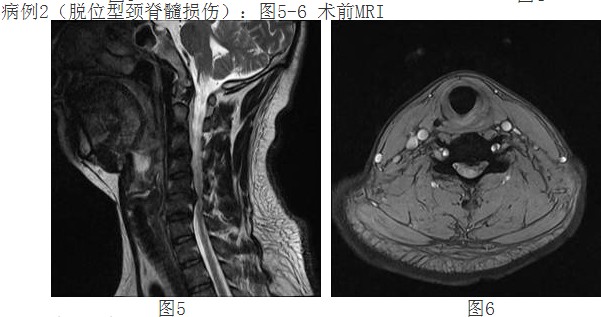

來自惠州農(nóng)村李阿婆有多年的頸椎病病史,一月前頸部癥狀加重出現(xiàn)頸痛及四肢麻木、刺痛,不能耐受,上肢手臂力量及握力下降。經(jīng)人介紹前來我院,經(jīng)惠州三院脊柱外科譚志宏主任仔細(xì)檢查,并結(jié)合頸椎MRI,明確診斷為頸4/5、頸5/6椎間盤突出癥并椎管狹窄,屬脊髓型頸椎病。同時(shí)認(rèn)為如果采取保守治療問題根本解決不了,只有手術(shù)治療才有康復(fù)的希望。頸椎手術(shù)在脊柱方面屬高難度、高風(fēng)險(xiǎn)手術(shù),在外科手術(shù)分級(jí)中屬于最高級(jí)別的Ⅳ級(jí)手術(shù)。